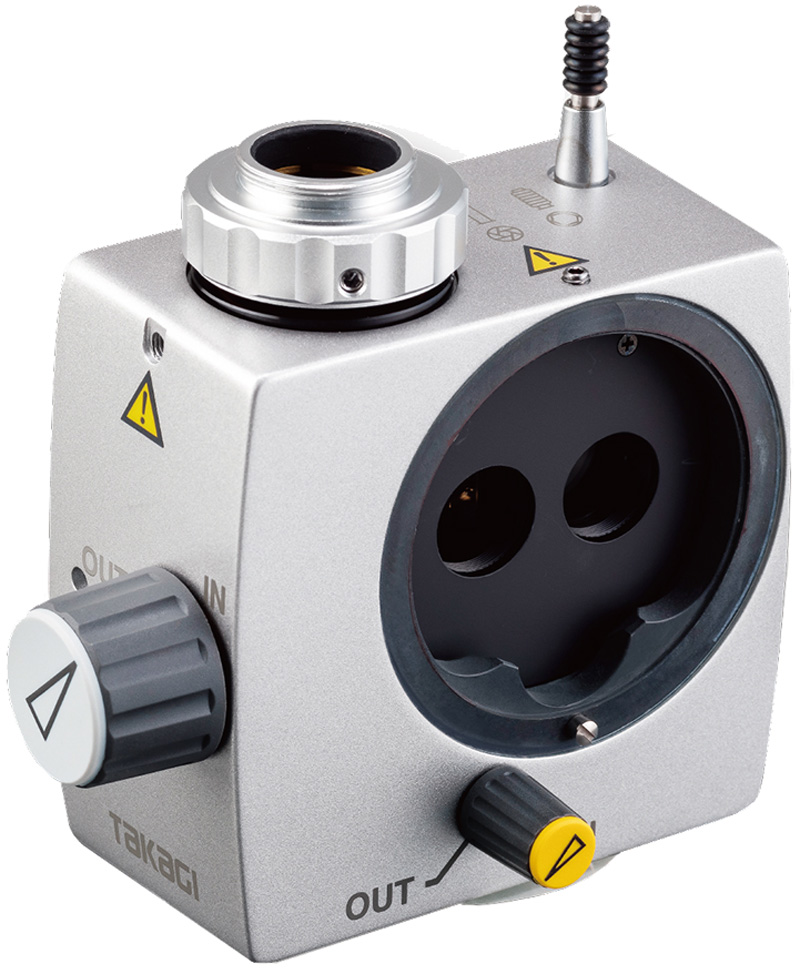

S10-17 コンビネーションTVカメラアダプター

Cマウントアダプターが標準で付属していますのでCマウントタイプのカメラであれば取り付けることができます。

※ 但し、本コンビネーションアダプタでは1/3インチ素子のCCDカメラの取付によりモニター上で最適な画角を得ることができるように設計されています。

IN側にツマミを廻すと接眼からの観察と共に左眼からの画像がカメラに接続されたモニターでも見ることができます。OUT側では接眼レンズからのみの観察となり、モニターでは映像を見ることができません。

CCDカメラを装着すると、止めネジで簡単にピント合わせができ、ピントを合わせやすくなります。

アダプター外周の3 ヶ所のセットネジによりCCDカメラ取付時の光軸センタリング調節を簡単に行うことができ、CCD素子の傾きによるモニター上の映像の位置ずれを修正することができます。

ビームスプリッター、 カメラアダプター、イエローフィルターをコンパクトなボディーに内蔵し一体化。接眼レンズから被検者までの距離を最小限におさえました。複数のアダプターを取り付けることによる操作性の悪さを解消しました。

ノブの押し引きで、カメラ側映像の焦点深度を変えることができます。ノブを引くと深度絞りはONになり、焦点深度は深くなります。(この際、映像は深度絞りOFFの際と比較し暗くなります) また、 ノブを押し込むと深度絞りはOFFになり、焦点深度は浅くなります。(この際、映像は深度絞りONの際と比較し明るくなります)

角膜の蛍光観察において、イエローフィルターを使用することによりコントラストの高い映像を得ることができます。当社のスリットランプ(700GL, 4ZL, 2ZL, 300XL)とのセッティングでは、スリットランプ内蔵のコバルトブルーフィルターとのベストマッチングにより更にコントラストの高い映像を得ることができます。